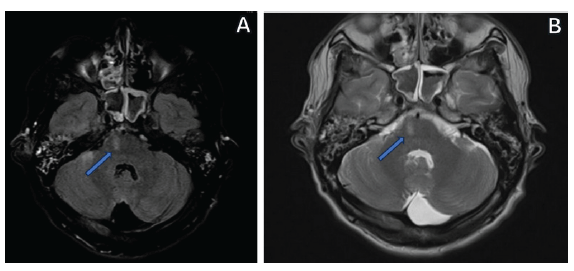

<p>En consideración de los signos focales y con la sospecha de afectación del tallo cerebral, se indicó una resonancia simple de cráneo, donde como hallazgo se demostró una imagen hiperintensa en secuencia T2 y FLAIR, localizada en la zona ventral derecha de la protuberancia (<xref ref-type="fig" rid="f3">figura 3</xref>), con lo cual se estableció el diagnóstico definitivo del síndrome de Millard-Gubler de origen traumático, por lo que se comenzó terapia antiinflamatoria con glucocorticoides endovenosos: metilprednisolona de 1000 mg cada día, por cinco días, y posteriormente, administración por vía oral de prednisona 60 de mg cada día, en dosis decreciente. Posterior al alta hospitalaria, se indicó fisioterapia motora y seguimiento por los servicios de Neurología y Oftalmología.</p>

<title>Resonancia magnética cerebral</title>

<attrib>Nota: en la <xref ref-type="fig" rid="f3">figura 3</xref>A se observa la resonancia en secuencia FLAIR y en la figura 3B se ve en secuencia T2, donde es visible la hiperintensidad en la región ventral derecha del puente (flecha azul).</attrib>